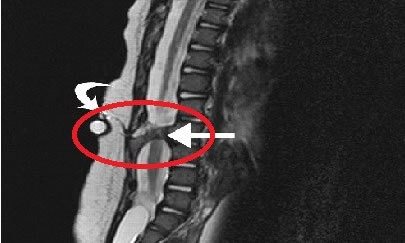

Миеломенингоцеле может возникнуть в любом месте вдоль оси позвоночника, но наиболее часто встречается в поясничной области. При этом состоянии позвоночник расщепляется, образуется выпячивание, напоминающее кисту. Стенки кисты представлены твердой и паутинной мозговыми оболочками, которые выпячиваются наружу через дефект в дужке позвонка.

Менингоцеле, или киста оболочек спинного мозга, вызывает неврологические нарушения в том случае, если она включает нервную ткань (в этом случае говорят о миеломенингоцеле). При полном незаращении нервной трубки возникает миелошизис – спинномозговая грыжа. Миеломенингоцеле возникает при неудачном закрытии нервной трубки, в результате чего образуется открытое повреждение или киста, которые включают измененный спинной мозг, нервные корешки, мозговые оболочки, тела позвонков и кожу.

Во II триместре информативность УЗИ повышается. Если же визуализация затруднена, может быть рекомендована магнитно-резонансная томография плода. Ее применение ограничивается движениями будущего ребенка, приводящими к нечеткости изображения. Поэтому необходимо выполнение исследования опытным врачом после специальной подготовки женщины.